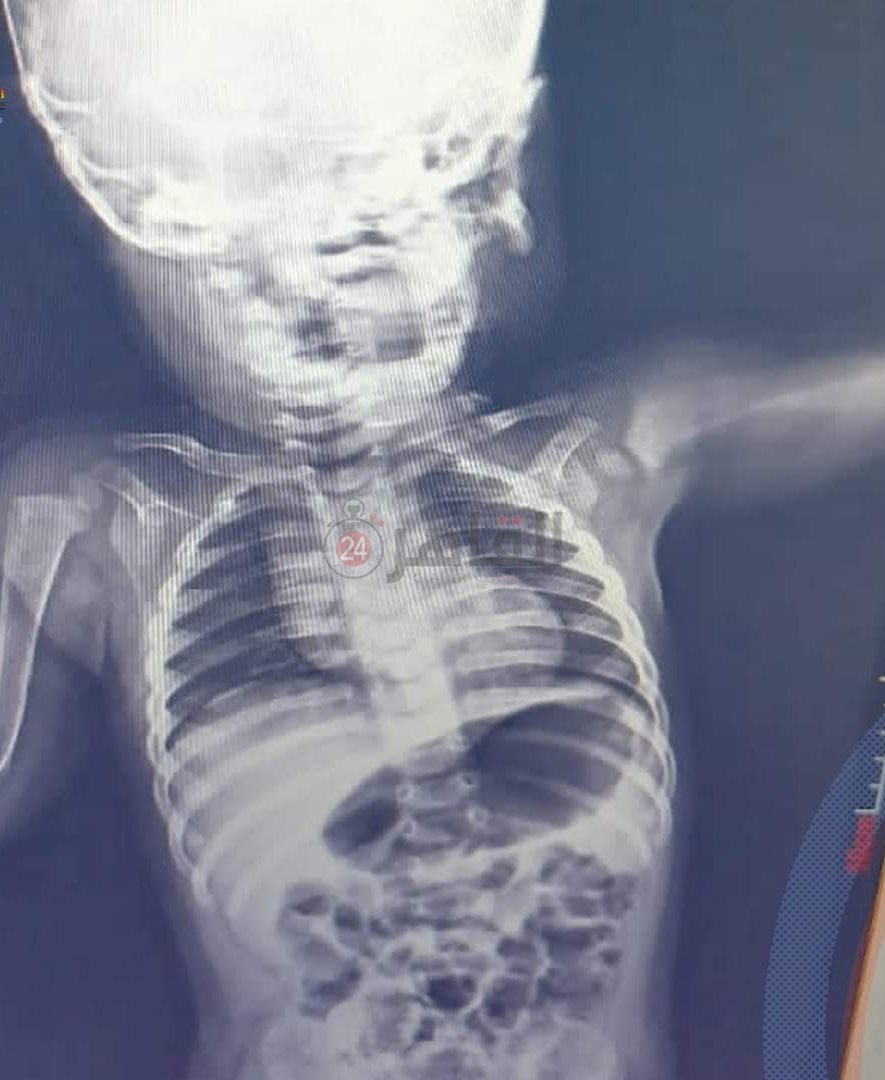

نجح فريق طبي بأحد مستشفيات مدينة الغردقة، في استخراج جسم معدني من معدة طفل يبلغ من العمر 8 أشهر.

وقال الدكتور رضا النجار رئيس مجلس إدارة المستشفى، إن قسم الجراحة والمناظير بالمستشفى نجح في استخراج جسم معدني صامولة من معدة طفل رضيع يبلغ من العمر 8 أشهر عن طريق منظار المعدة تحت مخدر كلي.

وأضاف النجار في تصريح خاص لـ القاهرة 24، أن عملية استخراج جسم غريب من طفل في هذه المرحلة العمرية تتم للمرة الأولى داخل مستشفيات البحر الأحمر، حيث قام بإجراء المنظار الدكتور محمود إدريس استشاري الجراحة والمناظير، وقام بتخدير الطفل الدكتور إبرام ممدوح استشاري التخدير.